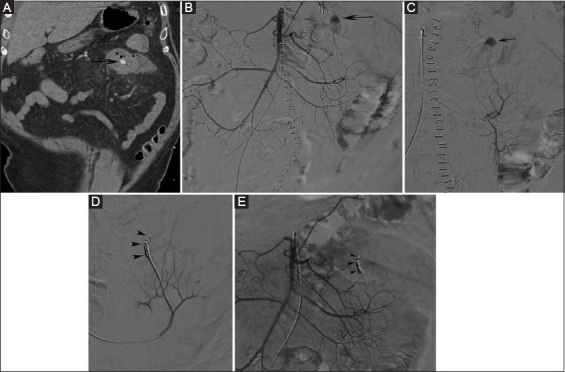

Background: This study evaluated the technical and clinical outcomes of transcatheter arterial embolization (TAE) in patients with acute small-bowel bleeding (SBB) and aimed to identify potential risk factors for early recurrent bleeding after TAE.

Methods: Thirty-one patients with SBB managed with TAE between January 2006 and December 2021 were included. Technical and clinical success was defined as angiographic occlusion of the bleeding artery and disappearance of clinical or laboratory signs of persistent bleeding without major complications. Complications were classified according to the Society of Interventional Radiology's guidelines. Kaplan-Meier estimates assessed overall survival, and logistic regression models determined risk factors for clinical success and early rebleeding.

Results: Technical and clinical success were achieved in 30/31 (97%) and 19 (61%), respectively. Early recurrent bleeding was present in 9 (29%) patients, and was treated by repeat embolization in 4 patients, conversion to surgery in 4, and comfort therapy in 1 patient. TAE-related small bowel ischemia requiring surgery was found in 2 (6.5%) patients. Thirty-day and in-hospital mortality were 19% (6/31) and 23% (7/31), respectively; overall 5-year estimated survival was 60%. Thrombocytopenia and elevated prothrombin time (PT)/activated partial thromboplastin time (aPTT) levels prior to TAE were identified as risk factors for clinical failure (P=0.0026 and P=0.027, respectively), and for residual or early recurrent bleeding (P<0.001 and P=0.01, respectively).

Conclusions: TAE is safe and effective for managing severe SBB; however, early recurrent bleeding was found in nearly one third of patients. Thrombocytopenia and elevated PT/aPTT levels were risk factors for early recurrent bleeding.